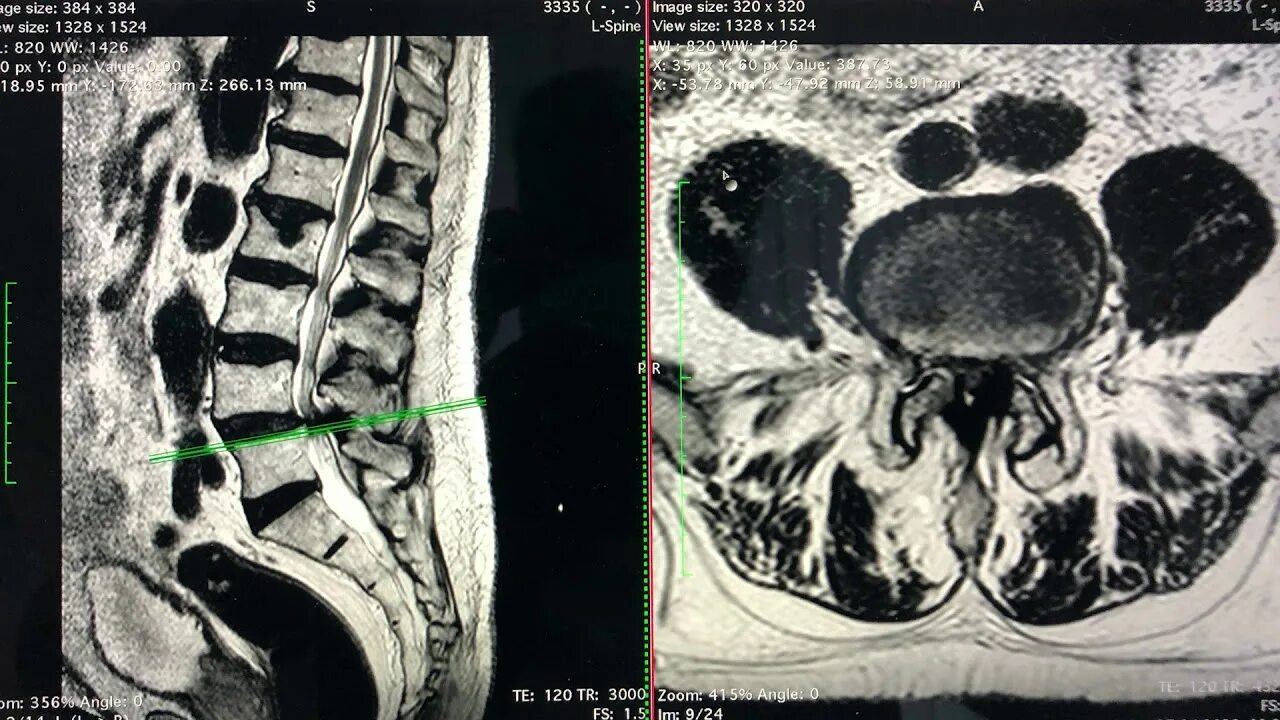

Лечение стеноза позвоночника без операции